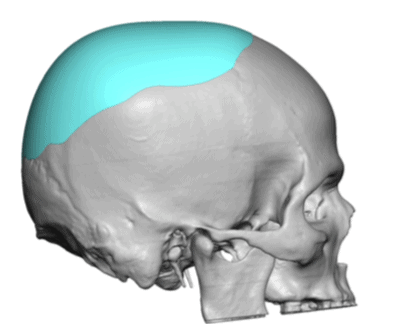

Desire for increased crown of head augmentation.

Crown of skull augmentation using a custom skull implant.

Desire for increased crown of head augmentation.

Crown of skull augmentation using a custom skull implant.